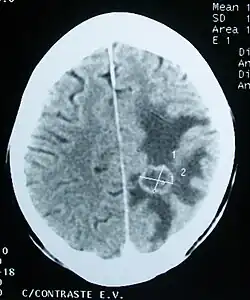

Imaging

Medical imaging plays a central role in the diagnosis of brain tumors. Early imaging methods – invasive and sometimes dangerous – such as pneumoencephalography and cerebral angiography have been replaced by non-invasive, high-resolution techniques, especially magnetic resonance imaging (MRI) and computed tomography (CT) scans.[42] MRI with contrast enhancement is the preferred imaging test in the diagnosis of brain tumors.[24][43] Glioblastomas usually enhance with contrast on T1 MRI weighted MRI imaging, and on T2 with FLAIR imaging showing hyperintense cerebral edema.[24] Low grade gliomas are usually hypointense on T1 MRI, and hyperintense with T2 with FLAIR MRI. Meningiomas are usually homogenously enhanced with dural thickening on MRI.[24]

Computed Tomography (CT) Scan – uses x-rays to take pictures from different angles and computer processing to combine the pictures into a 3D image. A CT scan usually serves as an alternative to MRI in cases where the patient cannot have an MRI due to claustrophobia or pacemaker. Compared to MRI, a CT scan shows a more detailed image of the bone structures near the tumor and can be used to measure the tumor's size.[51] Like an MRI, a contrast dye may also be injected into the veins or ingested by mouth before a CT scan to better outline any tumors that may be present. CT scans use contrast materials that are iodine-based and barium sulfate compounds. The downside of using CT scans as opposed to MRI is that some brain tumors do not show up well on CT scans because some intra-axial masses are faint and resemble normal brain tissue. In some scenarios, brain tumors in CT scans may be mistaken for infarction, infection, and demyelination. To suspect that an intra-axial mass is a brain tumor instead of other possibilities, there must be unexplained calcifications in the brain, preservation of the cortex, and disproportionate mass effect.[52]